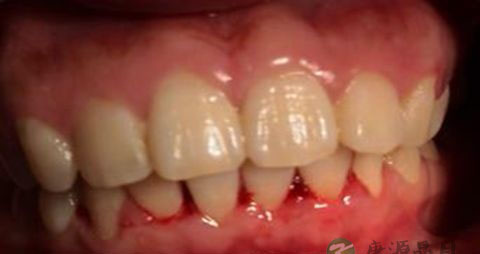

1、菌斑、牙石的局部刺激。菌斑、牙石的聚集,可由食物嵌塞、不良修复体、不良的口腔卫生习惯等引发,引起牙周组织炎症,如菌斑性牙龈炎、牙周炎等。

2、其他局部刺激因素(非菌斑牙石)及不良习惯。机械、化学、不良修复体、不良充填体、不良矫治器及张口呼吸等的刺激下,引发局部炎症,如增生性龈炎、牙周炎等。

3、局部组织过敏。局部接触过敏原时,引发过敏反应,波及牙龈时,牙龈红肿极易出血。如浆细胞性龈炎。

5、内分泌的改变。在性激素升高、孕酮激素升高的影响下,使牙龈组织在轻微刺激下,引发非特异性炎症,导致牙龈出血、渗出增多、牙龈增生等。如青春期龈炎、妊娠期龈炎及牙龈瘤。